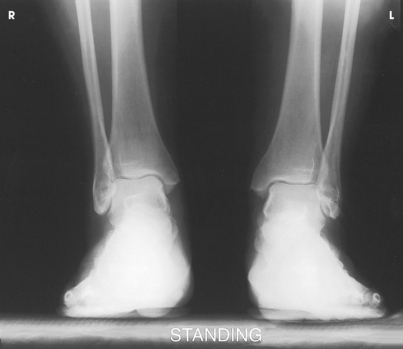

This projection is performed to identify ankle joint space narrowing with weight-bearing.

Structures shown: The resulting image shows an AP projection of both ankle joints and the relationship of the distal tibia and fibula with weight-bearing. It also shows side-to-side comparison of the joint (Fig. 6-110).